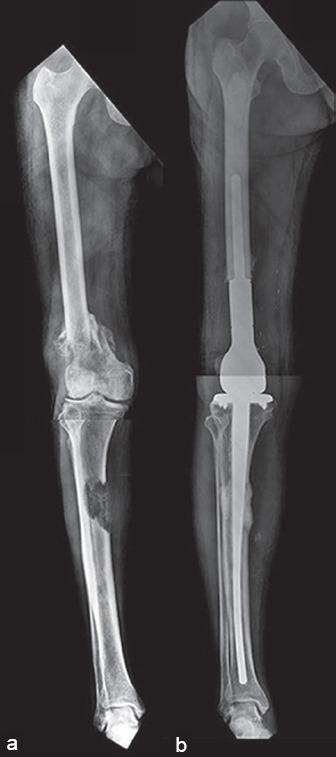

Skeletal metastasis is a common cause of severe morbidity, reduction in quality of life (QOL) and often early mortality. Its prevalence is rising due to a higher rate of diagnosis, better systemic treatment, longer lives with the disease and higher disease burden rate. As people with cancer live longer and with rising sensitivity of body imaging and surveillance, the incidence of pathological fracture, metastatic epidural cord compression is rising and constitutes a challenge for the orthopedic surgeon to maintain their QOL. Metastatic disease is no longer a death sentence condemning patients to "terminal care." In the era of multidisciplinary care and effective systemic targeted and nontargeted therapy, patient expectations of QOL, even during palliative end of care period is high. We lay emphasis on proving the diagnosis of metastasis by biopsy and histopathology and discuss imaging modalities to help estimate fracture risk and map disease extent. This article discusses at length the evidence and decision-making process of various modalities to treat skeletal metastasis. The modalities range from radiation including image-guided, stereotactic and whole body radiation, systemic targeted or hormonal therapy, spinal decompression with or without stabilization, extended curettage with stabilization, resection in select cases with megaprosthetic or biological reconstruction, percutaneous procedures using radio frequency ablation, cementoplasties and discusses the role of emerging modalities like high frequency ultrasound-guided ablation, cryotherapy and whole body radionuclide therapy. The focus lies on the role of multidisciplinary care, which considers complex decisions on patient centric prognosis, comorbidities, cost, feasibility and expectations in order to maximize outcomes on QOL issues.

骨转移是导致严重发病、生活质量(QOL)下降以及常出现早期死亡的常见原因。由于诊断率提高、全身治疗效果更好、患者带病生存时间延长以及疾病负担率上升,其患病率正在上升。随着癌症患者生存期延长以及身体成像和监测的敏感性提高,病理性骨折、转移性硬膜外脊髓压迫的发生率正在上升,这对骨科医生维持患者的生活质量构成了挑战。转移性疾病不再是宣判患者“临终关怀”的死刑判决。在多学科护理以及有效的全身靶向和非靶向治疗时代,即使在姑息性临终关怀阶段,患者对生活质量的期望也很高。我们强调通过活检和组织病理学来证实转移瘤的诊断,并讨论有助于评估骨折风险和描绘疾病范围的成像方式。本文详细讨论了治疗骨转移的各种方式的证据和决策过程。这些方式包括放疗,如影像引导放疗、立体定向放疗和全身放疗、全身靶向或激素治疗、有或无内固定的脊柱减压、扩大刮除术加内固定、在某些病例中进行假体或生物重建的切除术、使用射频消融、骨水泥成形术的经皮手术,并讨论了高频超声引导消融、冷冻疗法和全身放射性核素治疗等新兴方式的作用。重点在于多学科护理的作用,它考虑以患者为中心的预后、合并症、成本、可行性和期望等复杂决策,以最大限度地提高生活质量相关问题的治疗效果。